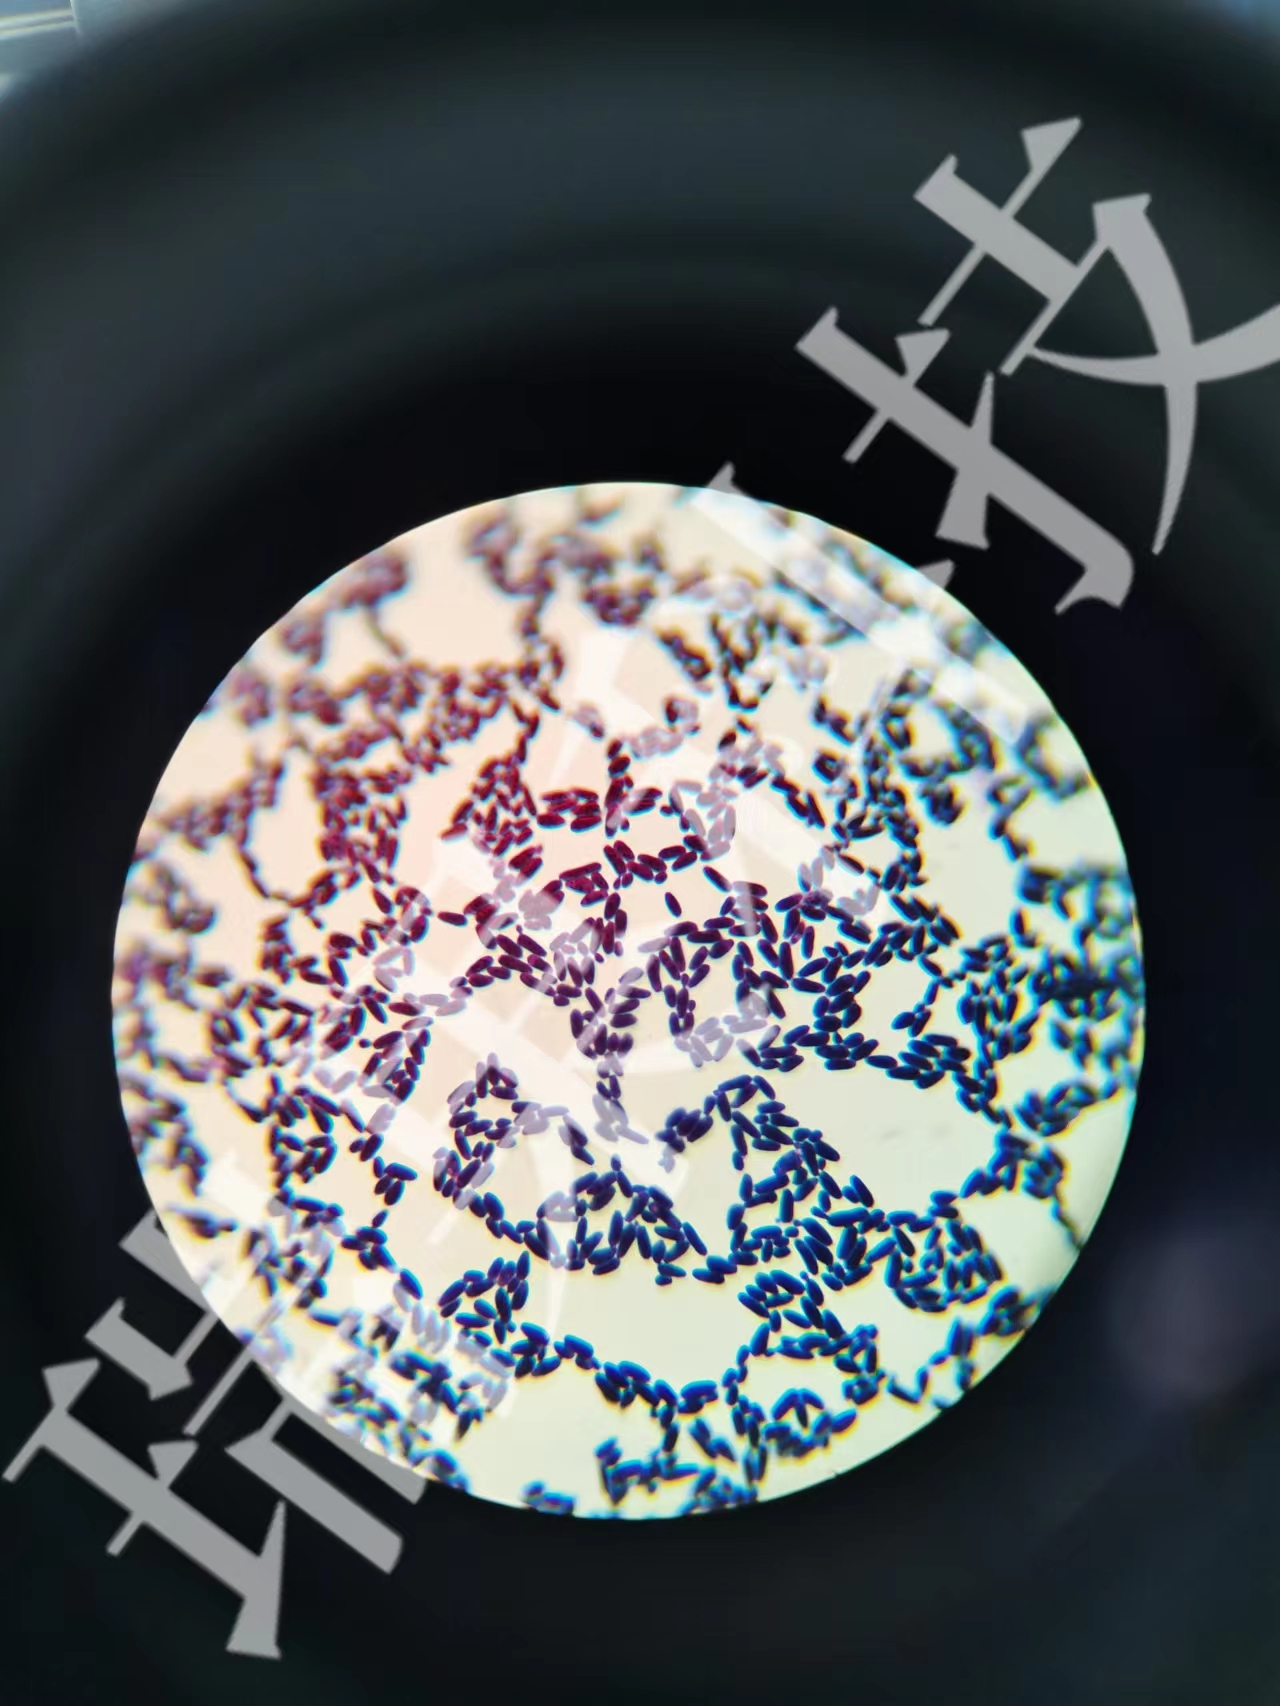

油红染色:油红染色一般指油红O脂肪染色法。油红O脂肪染色法是指在日常病理诊断和科研工作中为了显示组织内的脂肪常采用油红O进行染色的方法,油红O为脂溶性染料,在脂肪内能高度溶解,可特异性的使组织内甘油三

油红染色:油红染色一般指油红O脂肪染色法。油红O脂肪染色法是指在日常病理诊断和科研工作中为了显示组织内的脂肪常采用油红O进行染色的方法,油红O为脂溶性染料,在脂肪内能高度溶解,可特异性的使组织内甘油三酯等中性脂肪着色。